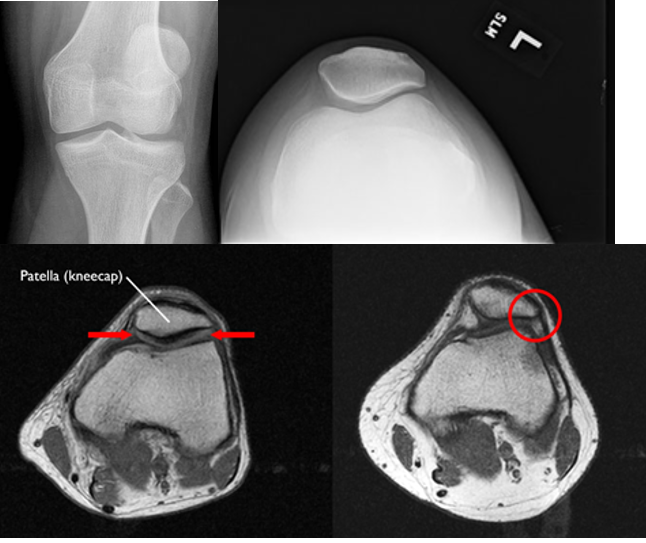

Patellofemoral Syndrome Imaging

A

• XR:

• Recommended views: AP, Lateral, Sunrise

• Look for:

• Lateral patellar tilt

• Shallow trochlear groove

• Signs of PFJ DJD = patellofemoral joint degenerative joint disease

• Keep in mind:

• Even with severe lateral subluxation, the patella reduces with flexion (sunrise view)

• AP view can be deceiving (positioning / rotation of the x-ray)

• CT / MRI: surgical planning